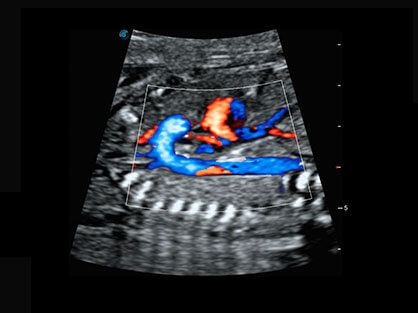

• AVC Follice卵泡自动测量

卵泡结构的自动识别和测量,可显示多组测量数据。